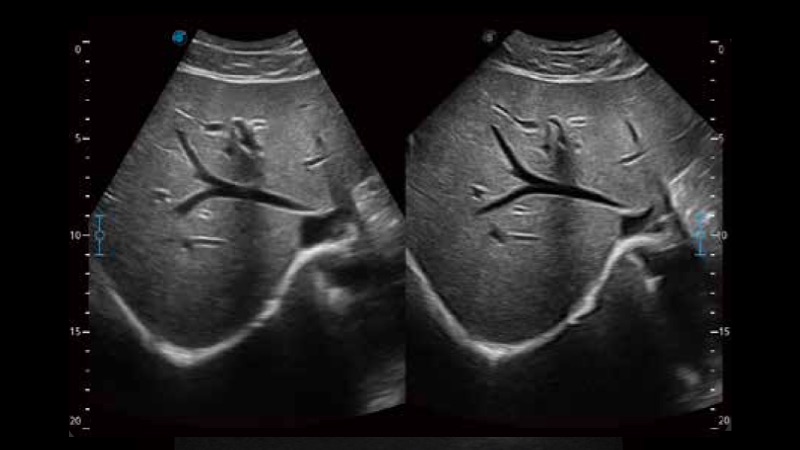

開(kāi)立醫(yī)療通過(guò)不斷的技術(shù)創(chuàng)新,為大眾的生命健康提供持續(xù)關(guān)愛(ài)。P12 Plus采用全新一代超聲成像平臺(tái),新平臺(tái)旨在將真實(shí)還原組織解剖結(jié)構(gòu)作為首要目標(biāo)。平臺(tái)采用全新集成化硬件模塊,搭載新一代芯片,系統(tǒng)性能得到大幅提升,為您的診斷提供了豐富的臨床信息。優(yōu)異的圖像表現(xiàn),豐富的探頭配置,全面的應(yīng)用功能,為您日常診斷提供了可靠的助手。